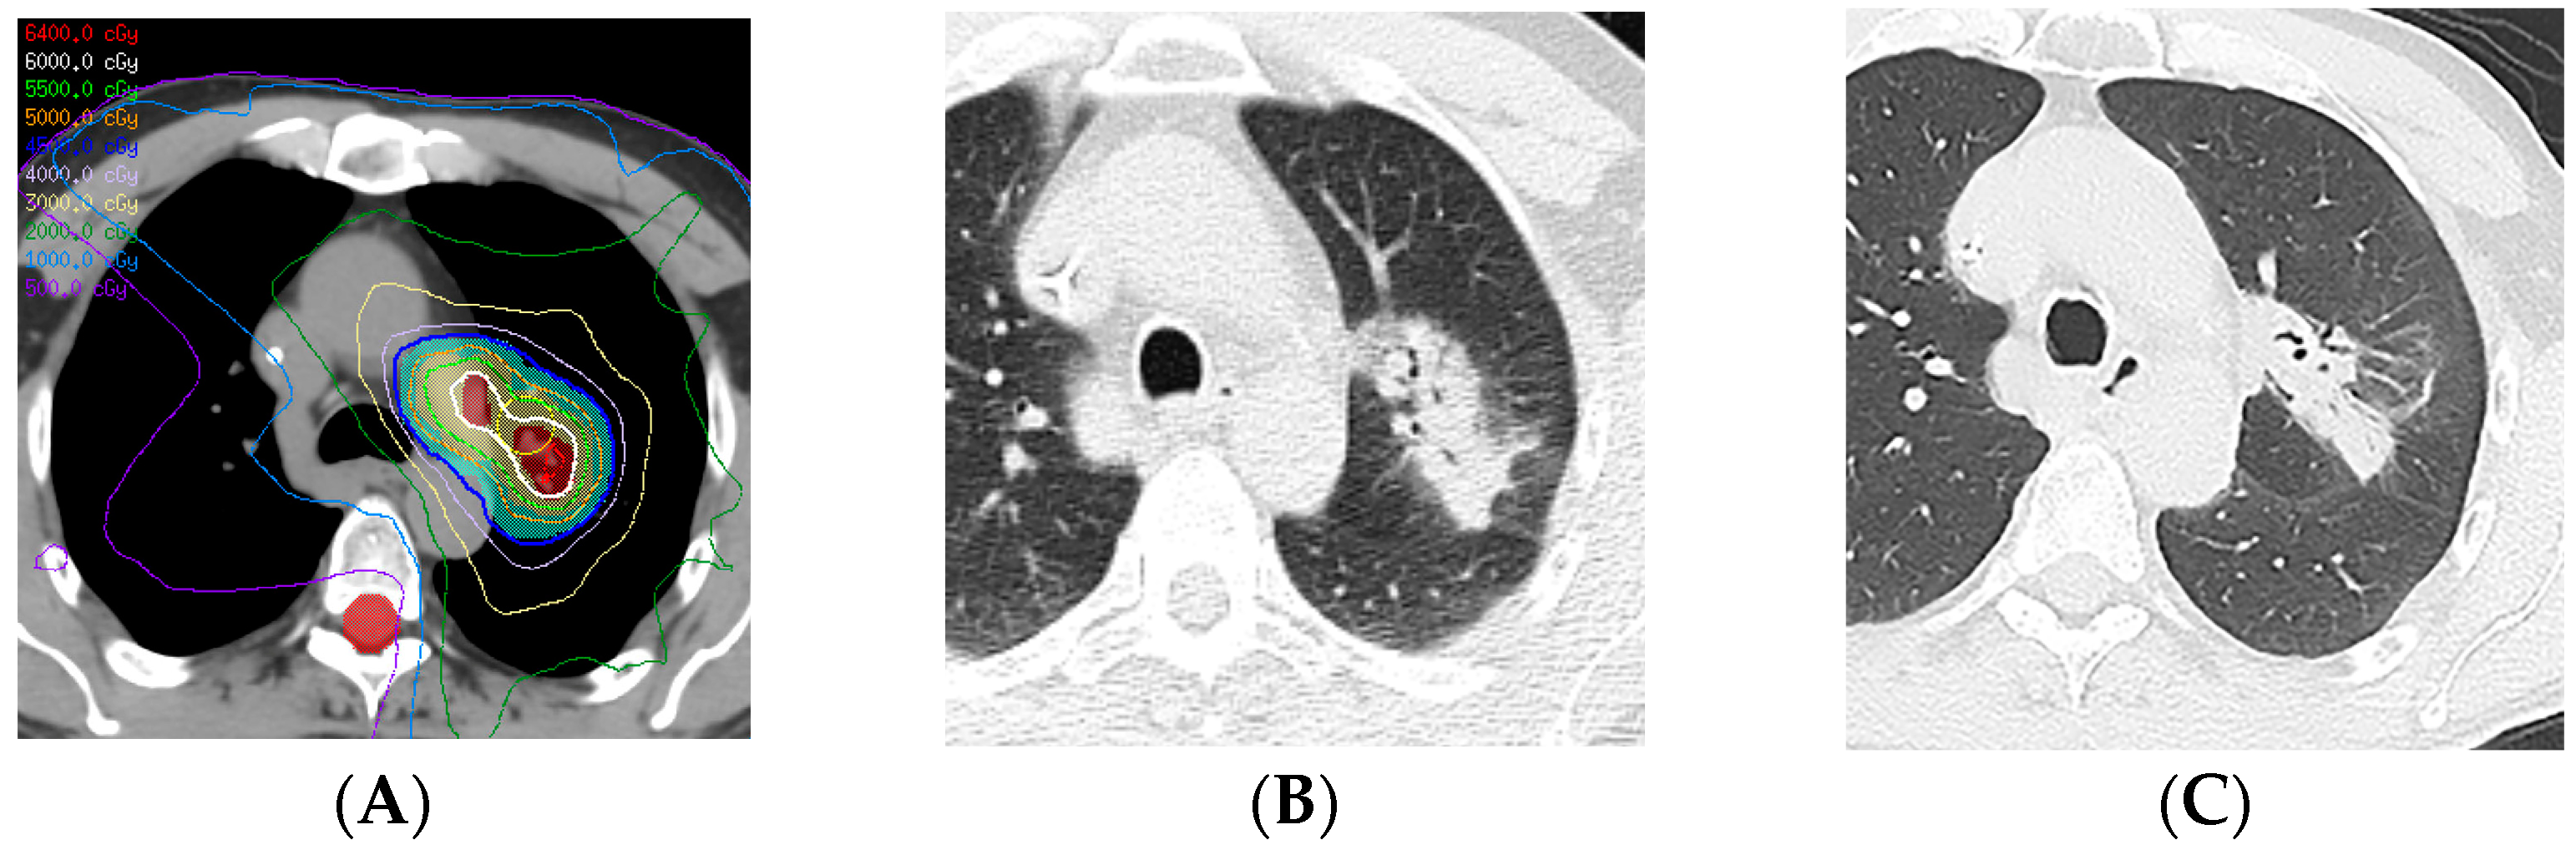

2.6. Proton Therapy

- Nakamura, N.; Hojo, H.; Inoue, K.; Hotta, K.; Zenda, S.; Baba, H.; Onozawa, M.; Motegi, A.; Nakamura, M.; Kibe, Y.; et al. Late radiological changes after passive scattering proton beam therapy for Stage I lung cancer. J. Radiat. Res. 2018, 59, 456–461. [Google Scholar] [CrossRef]